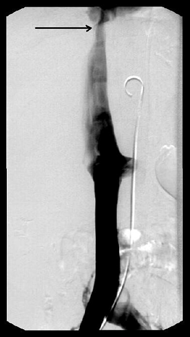

Основные достоинства МРТ — неинвазивность, безвредность, трехмерный характер получения изображений. Однако этот метод является одним из самых дорогостоящих, и о применении МРТ при опухолях надпочечников существуют разноречивые мнения. По мнению Nakao Y.et al. (1993), МРТ перспективна для выявления опухолей малых размеров, а Н. Лавин (Эндокринология, 1999) считает, что МРТ в некоторых случаях дополняет результаты КТ, но при малых размерах опухоли надпочечника чувствительность этого метода не превышает чувствительности КТ. Однако, несмотря на использование различных инструментальных методов, точный диагноз, особенно при гормонально-неактивных опухолях, позволяет установить лишь морфологическое исследование, которое возможно при исследовании материала, полученного при аспирационной тонкоигольной биопсии под контролем УЗИ или КТ (Giron J., 1997; Petronio R., 1985) (рис. 10). Точность метода равняется 80–90% (Gonczi I. et al., 1987).

Рисунок 10. Тонкоигольная пункция опухоли (адренокортикальный рак) левого надпочечника под контролем КТ

Однако при гормонально-активных опухолях выполнение биопсии чревато развитием криза (Хитрова А.Н., 1996).